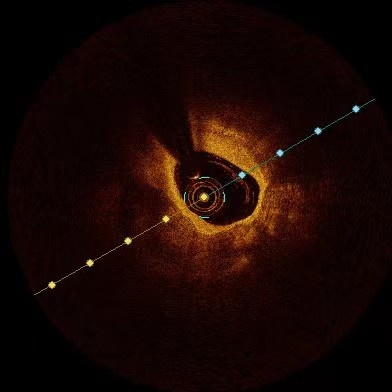

在球囊扩张开通闭塞血管的同时,可以看到患者的前降支非常发达,近段弥漫的瘤样扩张、血管钙化合并中段重度狭窄。使用血管内超声可以看到患者狭窄存在360°钙化。这样的病变是心血管内科介入医生最为头痛的。重度钙化可导致支架通过困难、支架膨胀不良等情况,容易发生支架脱载、急性支架内血栓、围术期心肌梗死等并发症。

厚厚的钙化斑块

钙化斑块中可见明显裂隙